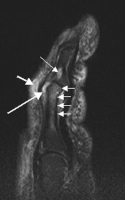

Magnetic resonance image of the index finger in psoriatic arthritis (mutilans form). Shown is a T2 weighted fat suppressed sagittal image. Focal increased signal (probable erosion) is seen at the base of the middle phalanx (long thin arrow). There is synovitis at the proximal interphalangeal joint (long thick arrow) plus increased signal in the overlying soft tissues indicating edema (short thick arrow). There is also diffuse bone edema (short thin arrows) involving the head of the proximal phalanx and extending distally down the shaft.